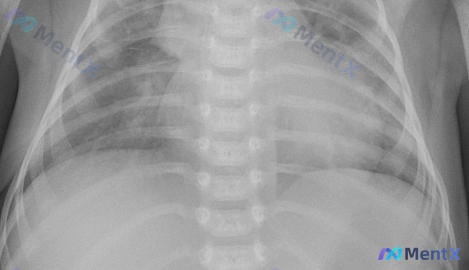

这个婴幼儿胸部X光片,第一眼只想到肺炎,第二个要排除什么高危情况?

整理了一份婴幼儿前后位(AP位)胸部X光片的影像资料,先不说结论,只看描述和分析里的几个点,想请大家先讨论一下: 基础背景:从胸廓和胸腺影(右上纵隔帆征)看,是婴幼儿。 影像核心表现: 1. 双肺纹理增多、增粗、紊乱,双肺门影增大、模糊; 2. 双肺中内带及肺门旁可见散在斑片状、云絮状密度增高影;...

整理到一份儿科胸部正位X光片资料,先纯看影像讨论一下,后面可以再补临床信息。 影像基本情况: - 儿科AP位(前后位)床旁片,吸气、对称、曝光度基本可 - 气管居中,胸廓骨骼、心影、膈肌/肋膈角未见明显异常 - 核心表现:双肺纹理明显增多增粗、走行紊乱;双肺野透亮度欠均匀,可见多发斑片状、云絮状影,...